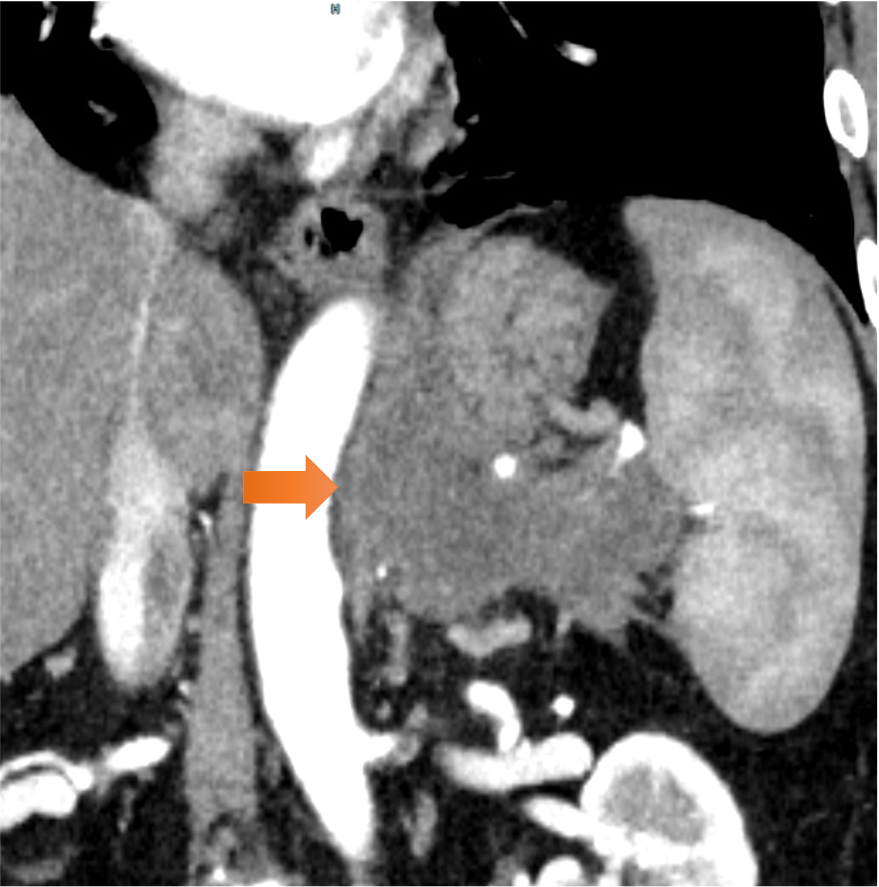

図3.脾動静脈浸潤

脾静脈は腫瘍により閉塞しており(→)、脾動脈は腫瘍と全周性に接触し、口径不整を認めた(⇨)。

図2.周辺臓器浸潤

左横隔膜脚(→)、胃穹隆部~体上部、左副腎、脾臓、腹膜との間の脂肪織の消失を認めた。